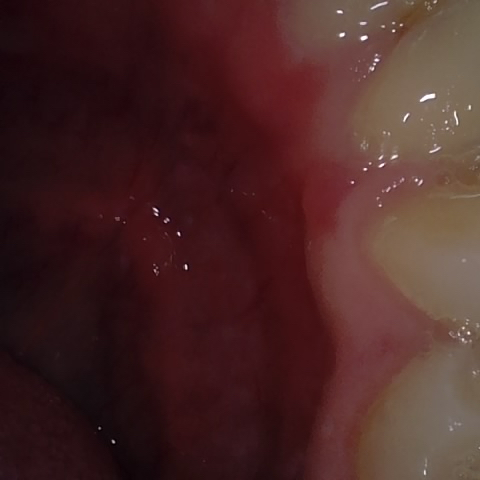

NHD20794

Annotated as "Good"